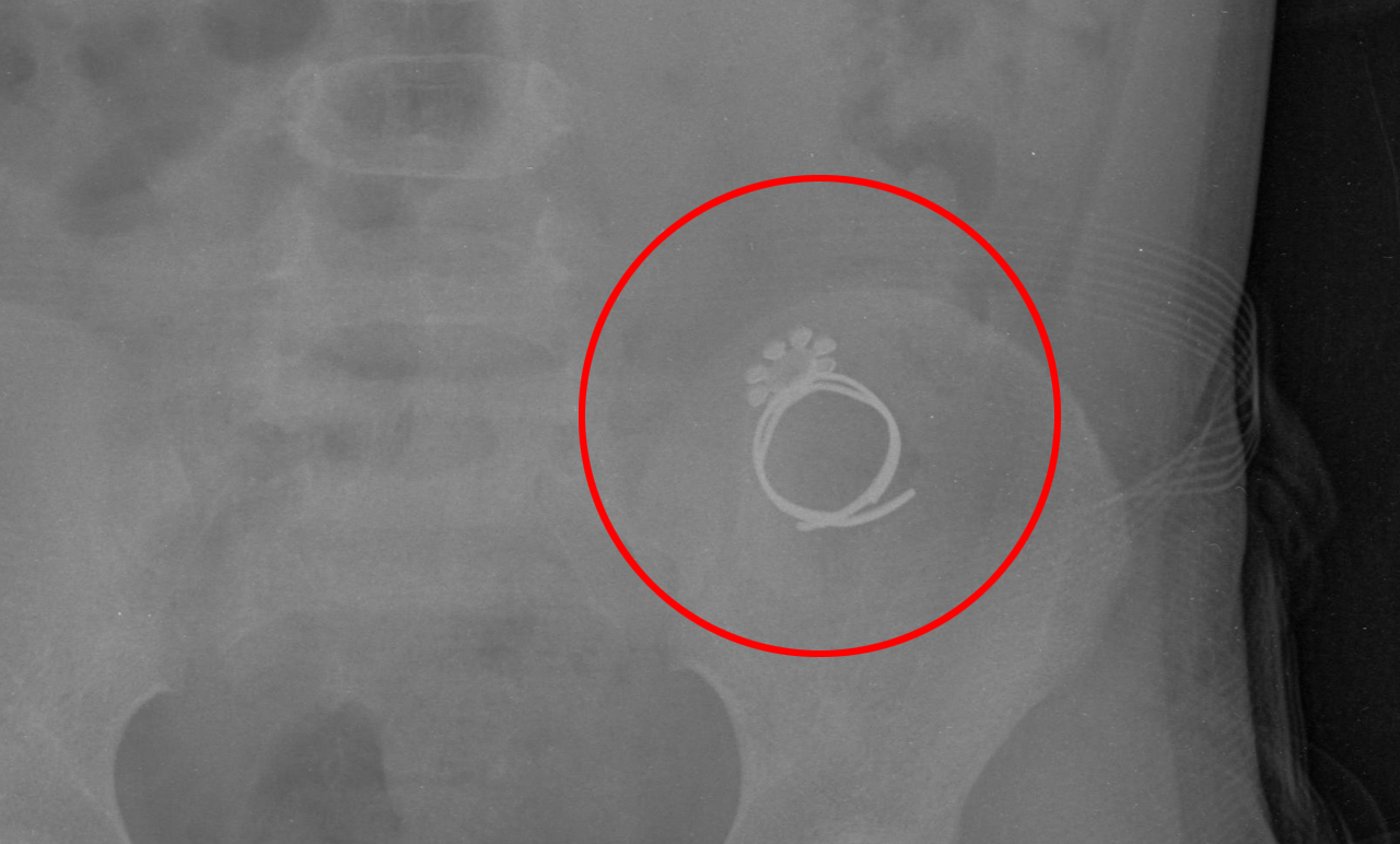

"רות הקטנה שלנו בלעה טבעת ונחנקה", מספרים בני המשפחה ל'כיכר השבת', "הטבעת, בצד אחד היתה חדה כסכין [ניתן לראות בתמונה] ויכלה לגרום לנזקים בלתי הפיכים. ה' יתברך ריחם עלינו ובחסדי שמים גדולים הטבעת ירדה לקיבה ויצאה בצורה טבעית".